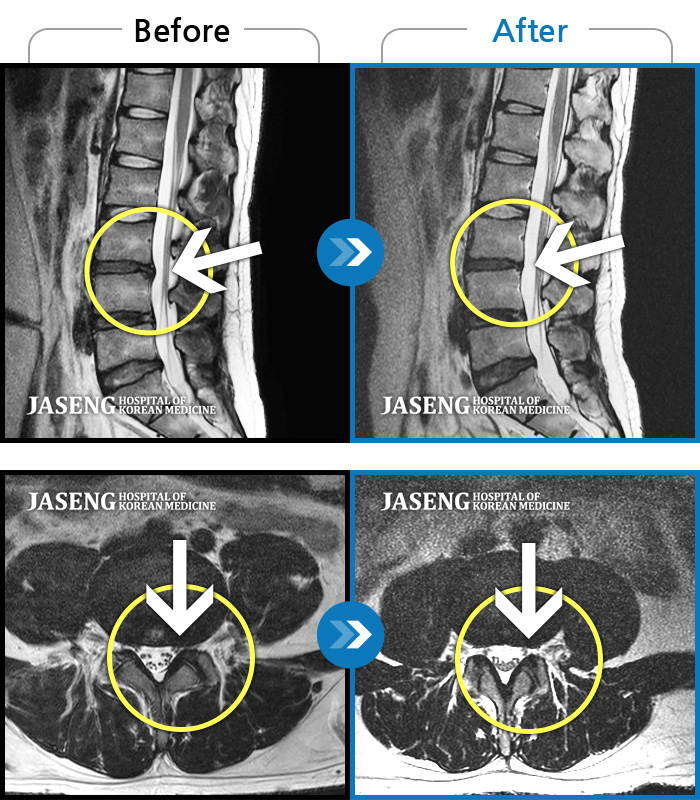

ȯںп Ǹ ǿ ԿǾ, ο ġ ۿ Ƿ ġḦ Ͻñ ٶϴ.